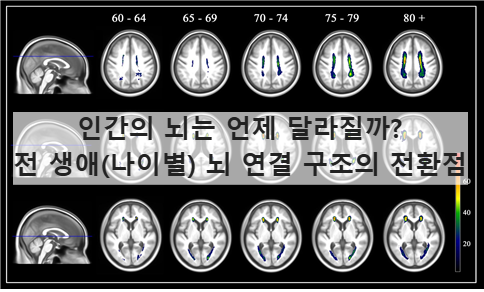

그림 1. 연구전반개요

전체 뇌 영상 데이터의 수집∙연령 분포∙분석 흐름을 보여준다.

0세부터 90세까지 4,216명의 확산 MRI 데이터를 통합하여

뇌 연결 네트워크 토폴로지의 비선형적 변화를 추적했다는 점을 시각화한다.